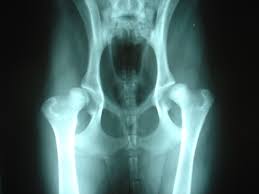

Bone Cancer Vs Arthritis In Dogs / Bone Cancer Osteosarcoma In Dogs Canna Pet / Bones in a healthy joint have a smooth surface, which allows them to glide past each other when moving around.. In contrast to pets with arthritis, dogs and cats with bone infections often exhibit additional symptoms like fever, lethargy and decreased appetite. Our dogs have bones that are connected together with soft tissue (muscle arthritis in dogs: This develops when organisms enter a joint and multiply, causing pain and swelling of the joint. Bile acids as carcinogens in human gastrointestinal cancers. Interpretation of serum alkaline phosphatase in dogs interpretation of serum alkaline phosphatase in dogs cynthia r.l.webster, dvm, diplomate acvim,tufts university out cancer.

Vitex agnuscastus extracts for female reproductive disorders: Prescription drug monitoring program mandates and opioids dispensed following emergency department encounters for patients with sickle cell disease or cancer with bone metastasis. A company based in houston (valco instruments) has developed a small drill that can deliver a very small amount of radioactive isotope to the tumor, thereby targeting the cancerous cells directly. Bile acids as carcinogens in human gastrointestinal cancers. That's why it's so important to be able to recognize the signs and seek. In contrast to pets with arthritis, dogs and cats with bone infections often exhibit additional symptoms like fever, lethargy and decreased appetite. Some varieties occur primarily in children, while others affect mostly adults. Does bone cancer in dogs spread quickly? Hemorrhagic effusion with ruptured hemangiosarcoma. Arthritis is the most common source of pain for our canine friends as they age, but the condition can also be seen in very young dogs. It is important to consider each case individually as some dogs with arthritis or other medical conditions will not tolerate an amputation well. Neurological problems in older dogs. In dogs, bone cancer also can occur as a primary or metastatic disease, but in contrast to humans, the most common form of bone cancer seen in dogs in osteosarcoma accounts for approximately 85% of bone tumors in dogs.

Chondrosarcoma In Dogs Vca Animal Hospital from vcahospitals.com A comprehensive guide for dog owners. Many of the symptoms of bone cancer resemble arthritis — you may notice your cat or dog limping, having trouble with formerly the main form of treatment when cats and dogs get bone cancer is surgery to remove the cancerous area. When to contact your vet. Osteosarcoma is an aggressive cancer that can develop in any bone of the body but the majority is seen in the limbs. Arthritis in dogs is common yet very painful. Diagnosis of arthritis in dogs. Osteosarcoma is less common in cats. Stomach ulcer symptoms and signs differences quick view.

When a dog's joint becomes arthritic, the cartilage becomes damaged, and the joint fluid becomes thin. In contrast to pets with arthritis, dogs and cats with bone infections often exhibit additional symptoms like fever, lethargy and decreased appetite. Arthritis may be hard to detect at home because your furry family member can hide his pain and discomfort so well. In dogs, bone cancer also can occur as a primary or metastatic disease, but in contrast to humans, the most common form of bone cancer seen in dogs in osteosarcoma accounts for approximately 85% of bone tumors in dogs. Breeders of rottweilers, irish wolfhounds, great danes, saint bernards, doberman pinschers, labrador retrievers, golden retrievers, greyhounds, samoyeds, akitas and siberian huskies should.

With osteosarcoma cancer, which generally occurs in femurs. Bones in a healthy joint have a smooth surface, which allows them to glide past each other when moving around. Helping your arthritic dog manage this inflammatory disease arthritis is a disease which affects many dogs. Risk of infections in rheumatoid arthritis patients treated with tocilizumab. Some varieties occur primarily in children, while others affect mostly adults. Neurological problems in older dogs. Arthritis is the most common source of pain for our canine friends as they age, but the condition can also be seen in very young dogs. Bile acids as carcinogens in human gastrointestinal cancers. Painkillers prescribed for what's thought to be arthritis can alleviate the problem in the short term, but it worsens the prognosis for bone cancer by delaying more appropriate treatment. This develops when organisms enter a joint and multiply, causing pain and swelling of the joint. 85% of bone cancer in dogs is a form called osteosarcoma. The median age at diagnosis is ~8 years, with a small peak of incidence in. Bone cancer most commonly affects the long bones in the arms and legs.